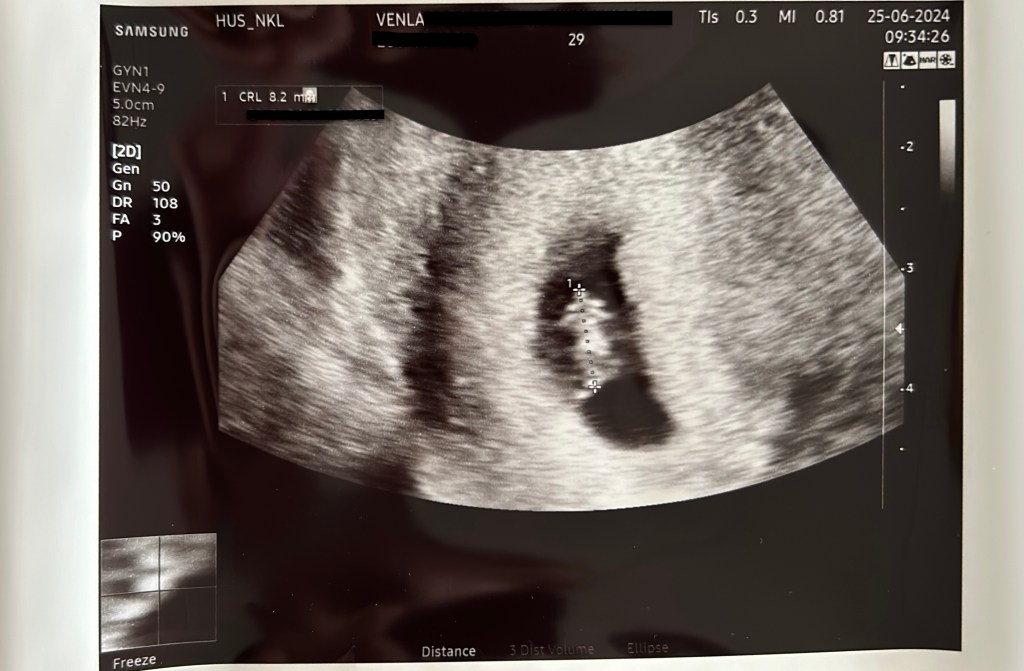

Tällä hetkellä olen siis edelleen raskaana ja tästä samasta pienestä vahvasta alkiosta on kehittynyt hyvinvoiva, terve sikiö. En voi uskoa tuuriamme ja vielä ajoittain tuntuu, että kohta se viedään meiltä pois. Koko ensimmäisen kolmanneksen ajan läsnä oli todella vahva menettämisen pelko. Vähitellen kun raskausmaha alkaa kasvaa, tilanne muuttuu kuitenkin todellisemmaksi. Näimme vauvamme sykkeen ensimmäisen kerran varhaisultrassa, joka tehtiin Tilkan lapsettomuuspoliklinikalla viisi viikkoa munasolupunktion jälkeen. Lääkärin mukaan kaikki vaikutti hyvältä. Hyperstimulaatio oli silloin edelleen päällä, minkä vuoksi munasarjat olivat jopa kasvaneet edellisestä ja lähentelivät nyt jo 8 senttimetriä! Onneksi vatsassa ei näkynyt enää nestettä.